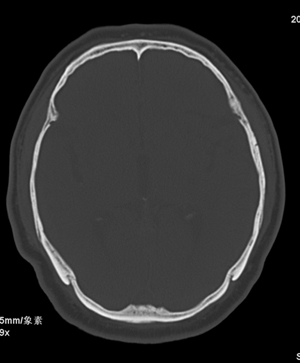

肢体活动肌力均正常。临床印象:脑血管病变。ct意见:脑软化灶,腔梗,请看看枕部病变是脑膜瘤,血管畸形还是其它

不象是软化灶.考虑水肿,病灶内有钙化,建议增强.

1.右基底节区脑软化灶。

2.右顶后部病变,脑膜瘤可能性大。

建议:强化扫描。

建议:强化扫描。不除外静脉窦血栓形成